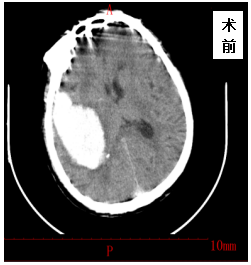

2021年03月04日,金洞乡桂花村村民张XX因突发高血压脑出血急诊来我院就诊,入院时患者意识障碍,左侧肢体偏瘫,急诊CT示:颅内大量出血,出血量约150ml,病情十分危重,患者随时会出现生命危险,需要紧急手术,内一科李太斌主任及时请外科杨继金副院长会诊,确定行急诊开颅血肿清除引流术,经以杨继金副院长为首的外科手术麻醉团队的共同努力,成功顺利的为该患者施行颅内血肿清除术,术后第二天患者神志逐渐恢复正常,左侧偏瘫肢体逐渐恢复正常,出院时,患者已经能自主站立行走,现已痊愈出院。